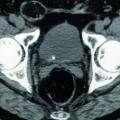

La NLPC consiste à introduire un néphroscope dans le rein à travers la paroi postérieure de l’abdomen par un tunnel mesurant 5 à 10 mm de diamètre. La fragmentation, effectuée par procédé endocorporel (laser ou ultrasons) est suivie de l’extraction. C’est le traitement de référence des calculs volumineux, supérieurs à 2 cm, et plus généralement complexes et coralliformes (fig. 5 et 6).

Les résultats ne sont quasiment pas corrélés à la taille de ces derniers.6 Elle peut être combinée à l’URSS dans le même temps opératoire pour en augmenter l’efficacité ou être la première étape d’une succession de traitements (les fragments résiduels, < 2 cm, peuvent être pris en charge ultérieurement par LEC ou URSS). Elle est contre-indiquée chez les patients sous anticoagulants et s’accompagne d’une morbidité essentiellement infectieuse et hémorragique. Toutefois, réalisée dans des centres experts, c’est une technique efficace et sûre.